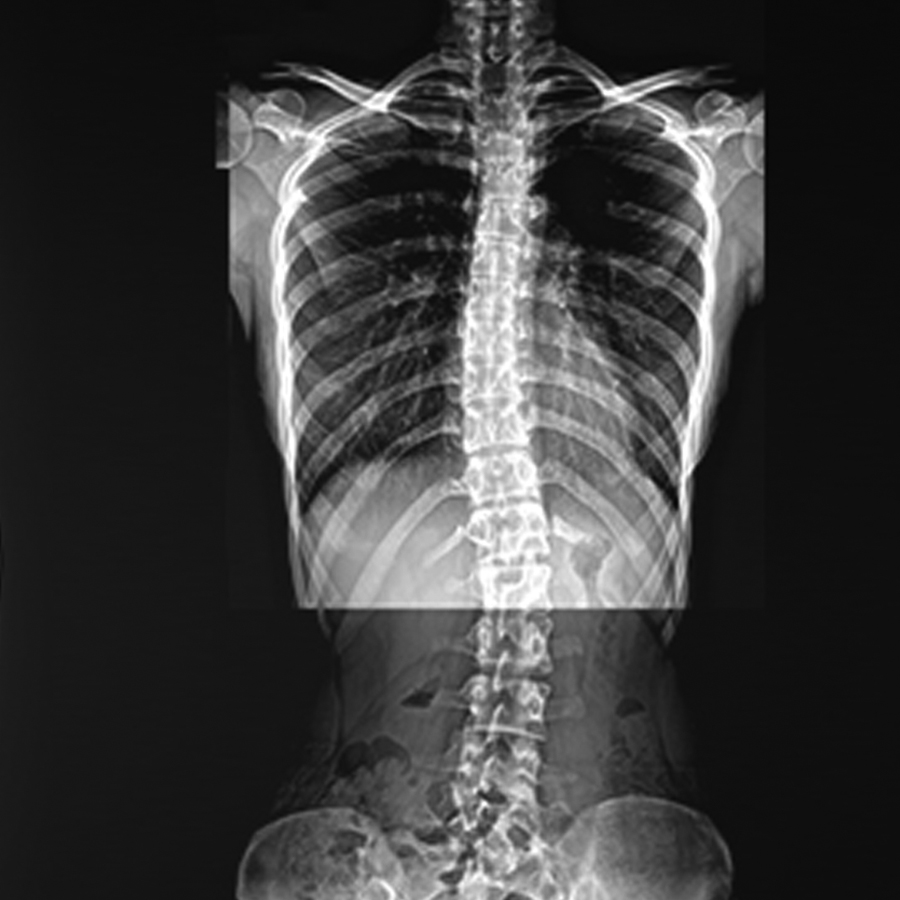

똑바로 앉아도 어깨의 위치가 다르거나 허리를 숙였을 때 척추가 휘어진 모양으로 보이는 현상이 성인뿐

만 아니라 청소년 사이에서 많이 발병되고 있고 정상적인 척추는 일자로 똑바로 서있어 몸 중심에 위치하게 됩니다.만약 척추가 일자가 아니라

옆으로 굽고 휘어있는 S자 상태를 척추측만증 또는 측만증 이라고 합니다. 발생 빈도는 전체 인구의약 2%~3% 정도에서 나타납니다.

척추측만증 증상

01앉아있는 자세가 한쪽으로 기울어진다.

02허리를 숙이면 등이나 허리가 한쪽으로 휜다.

03앞에서볼 때 가슴이 비대칭이된다. (여성의 경우 한쪽가슴발달이 적다)

04똑바로 서있을 때 양쪽어깨, 쇄골, 골반의 높이가 다르다.

05신발한쪽이 빨리 닳는다